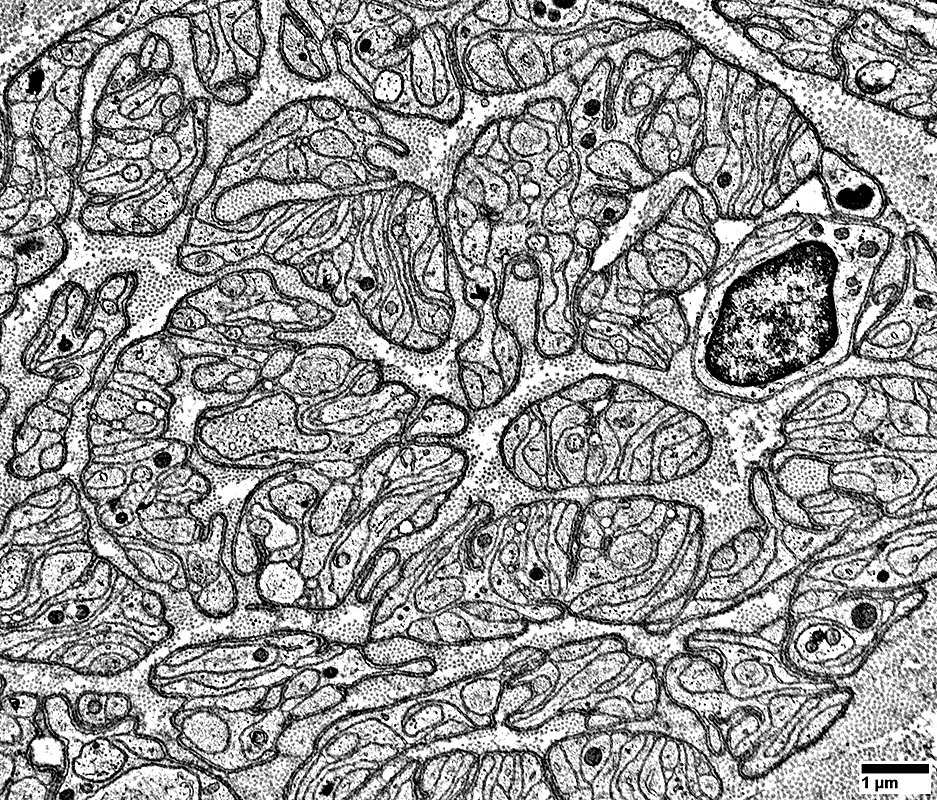

Bands of Büngner: Collections of processes from Denervated Schwann Cells

Clusters of Schwann cell processes are contained within a layer of basal lamina

From: R Schmidt

Schwann cell processes are contained within a layer of basal lamina (Arrows)

Schwann cell processes: Multiple collections

Schwann cell processes: Within layer of basal lamina